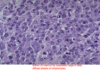

Diffuse Large B Cell Lymphoma (NHL)

Burkitt Lymphoma (NHL)

34

Burkitt Lymphoma (NHL)